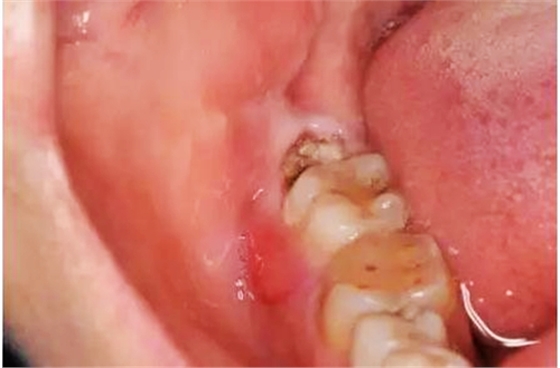

圖1.術(shù)前口內(nèi)觀:48合面齲壞,牙冠萌出1/2,37頰側(cè)牙齦紅腫。